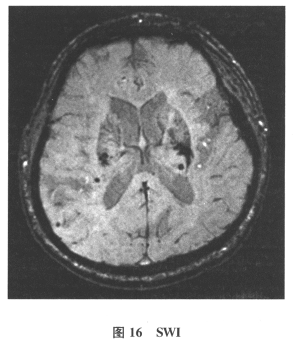

C.多发性微出血

[单选题]患者男,61岁。因“发作性头晕2年,加重伴记忆力下降、走路不稳3月余”就诊。查体:BP140/70mmHg;意识清楚,构音障碍,近期记忆力及远期记忆力

[多选题]患者男,61岁。因“发作性头晕2年,加重伴记忆力下降、走路不稳3月余”就诊。查体:BP140/70mmHg;意识清楚,构音障碍,近期记忆力及远期记忆力